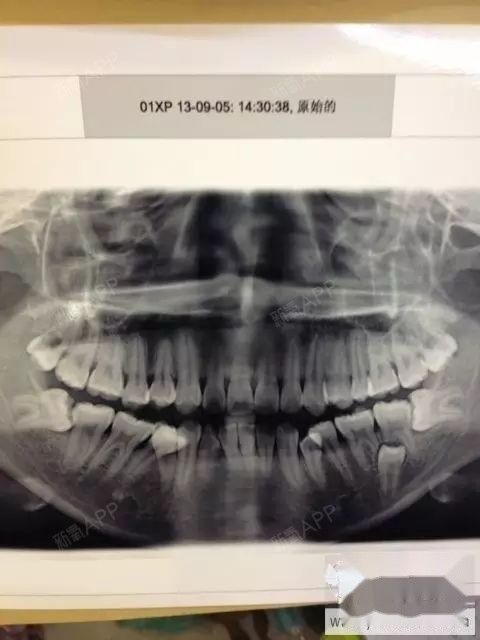

关于看牙拍牙片必须知道的那些事儿

看30岁缺三颗大牙的矫正案例原来缺牙不是只能做种植牙哦

大家看智齿旁边的一颗大牙下面还有一颗牙齿!这个要怎么办?

矫正第二磨牙(大牙)_智齿_磨牙_拔智齿_医疗健康_医疗健康其他